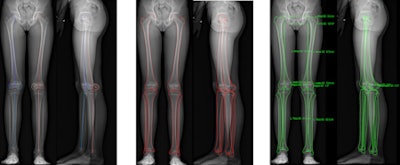

Another method, biplanar low-dose DR with a 2D/3D system (EOS Imaging), uses two orthogonal sources of radiation and linear digital detectors that produce two orthogonal x-ray images of the lower limbs in the standing position. The system generates surface 3D reconstructions and measurements of the lower limbs, and 2D measurements of the lower limbs, automatically generated from 3D reconstructions.

The group took 3D measurements of eight dried bones, analyzing them with the EOS system using stereoscopic software and comparing the measurements with 3D CT. Also, 47 lower limbs of children and adolescents were studied using biplanar low-dose x-ray 2D and 3D measurements. Both parts of the study were evaluated for femoral length, tibial length, femoral mechanical angle, tibial mechanical angle, frontal and lateral knee angulations, and the femoral neck-shaft angle.

The researchers found the 3D comparison between the EOS system and CT showed no significant differences in femoral length, tibial length, femoral mechanical angle, tibial mechanical angle, frontal knee angulation, lateral knee angulation, and femoral neck-shaft angle.

However, 2D and 3D measurements from the EOS system demonstrated significant differences in tibial length, femoral mechanical angle, and femoral neck-shaft angle.